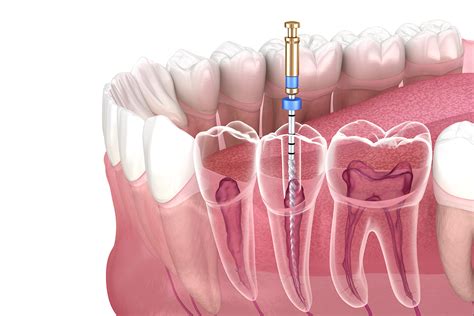

3. Access Opening: A small hole is made in the crown of the tooth to reach the pulp chamber.

4. Cleaning and Shaping: The infected pulp and bacteria are removed, and the canals are shaped for a filling.

5. Disinfection: The canals are washed with specialized antimicrobial solutions.

6. Filling and Sealing: The canals are filled with a biocompatible material called gutta-percha.

7. Restoration: A crown or permanent filling is placed to protect the structural integrity of the tooth.